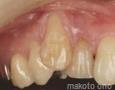

Pictures

1 Weeks